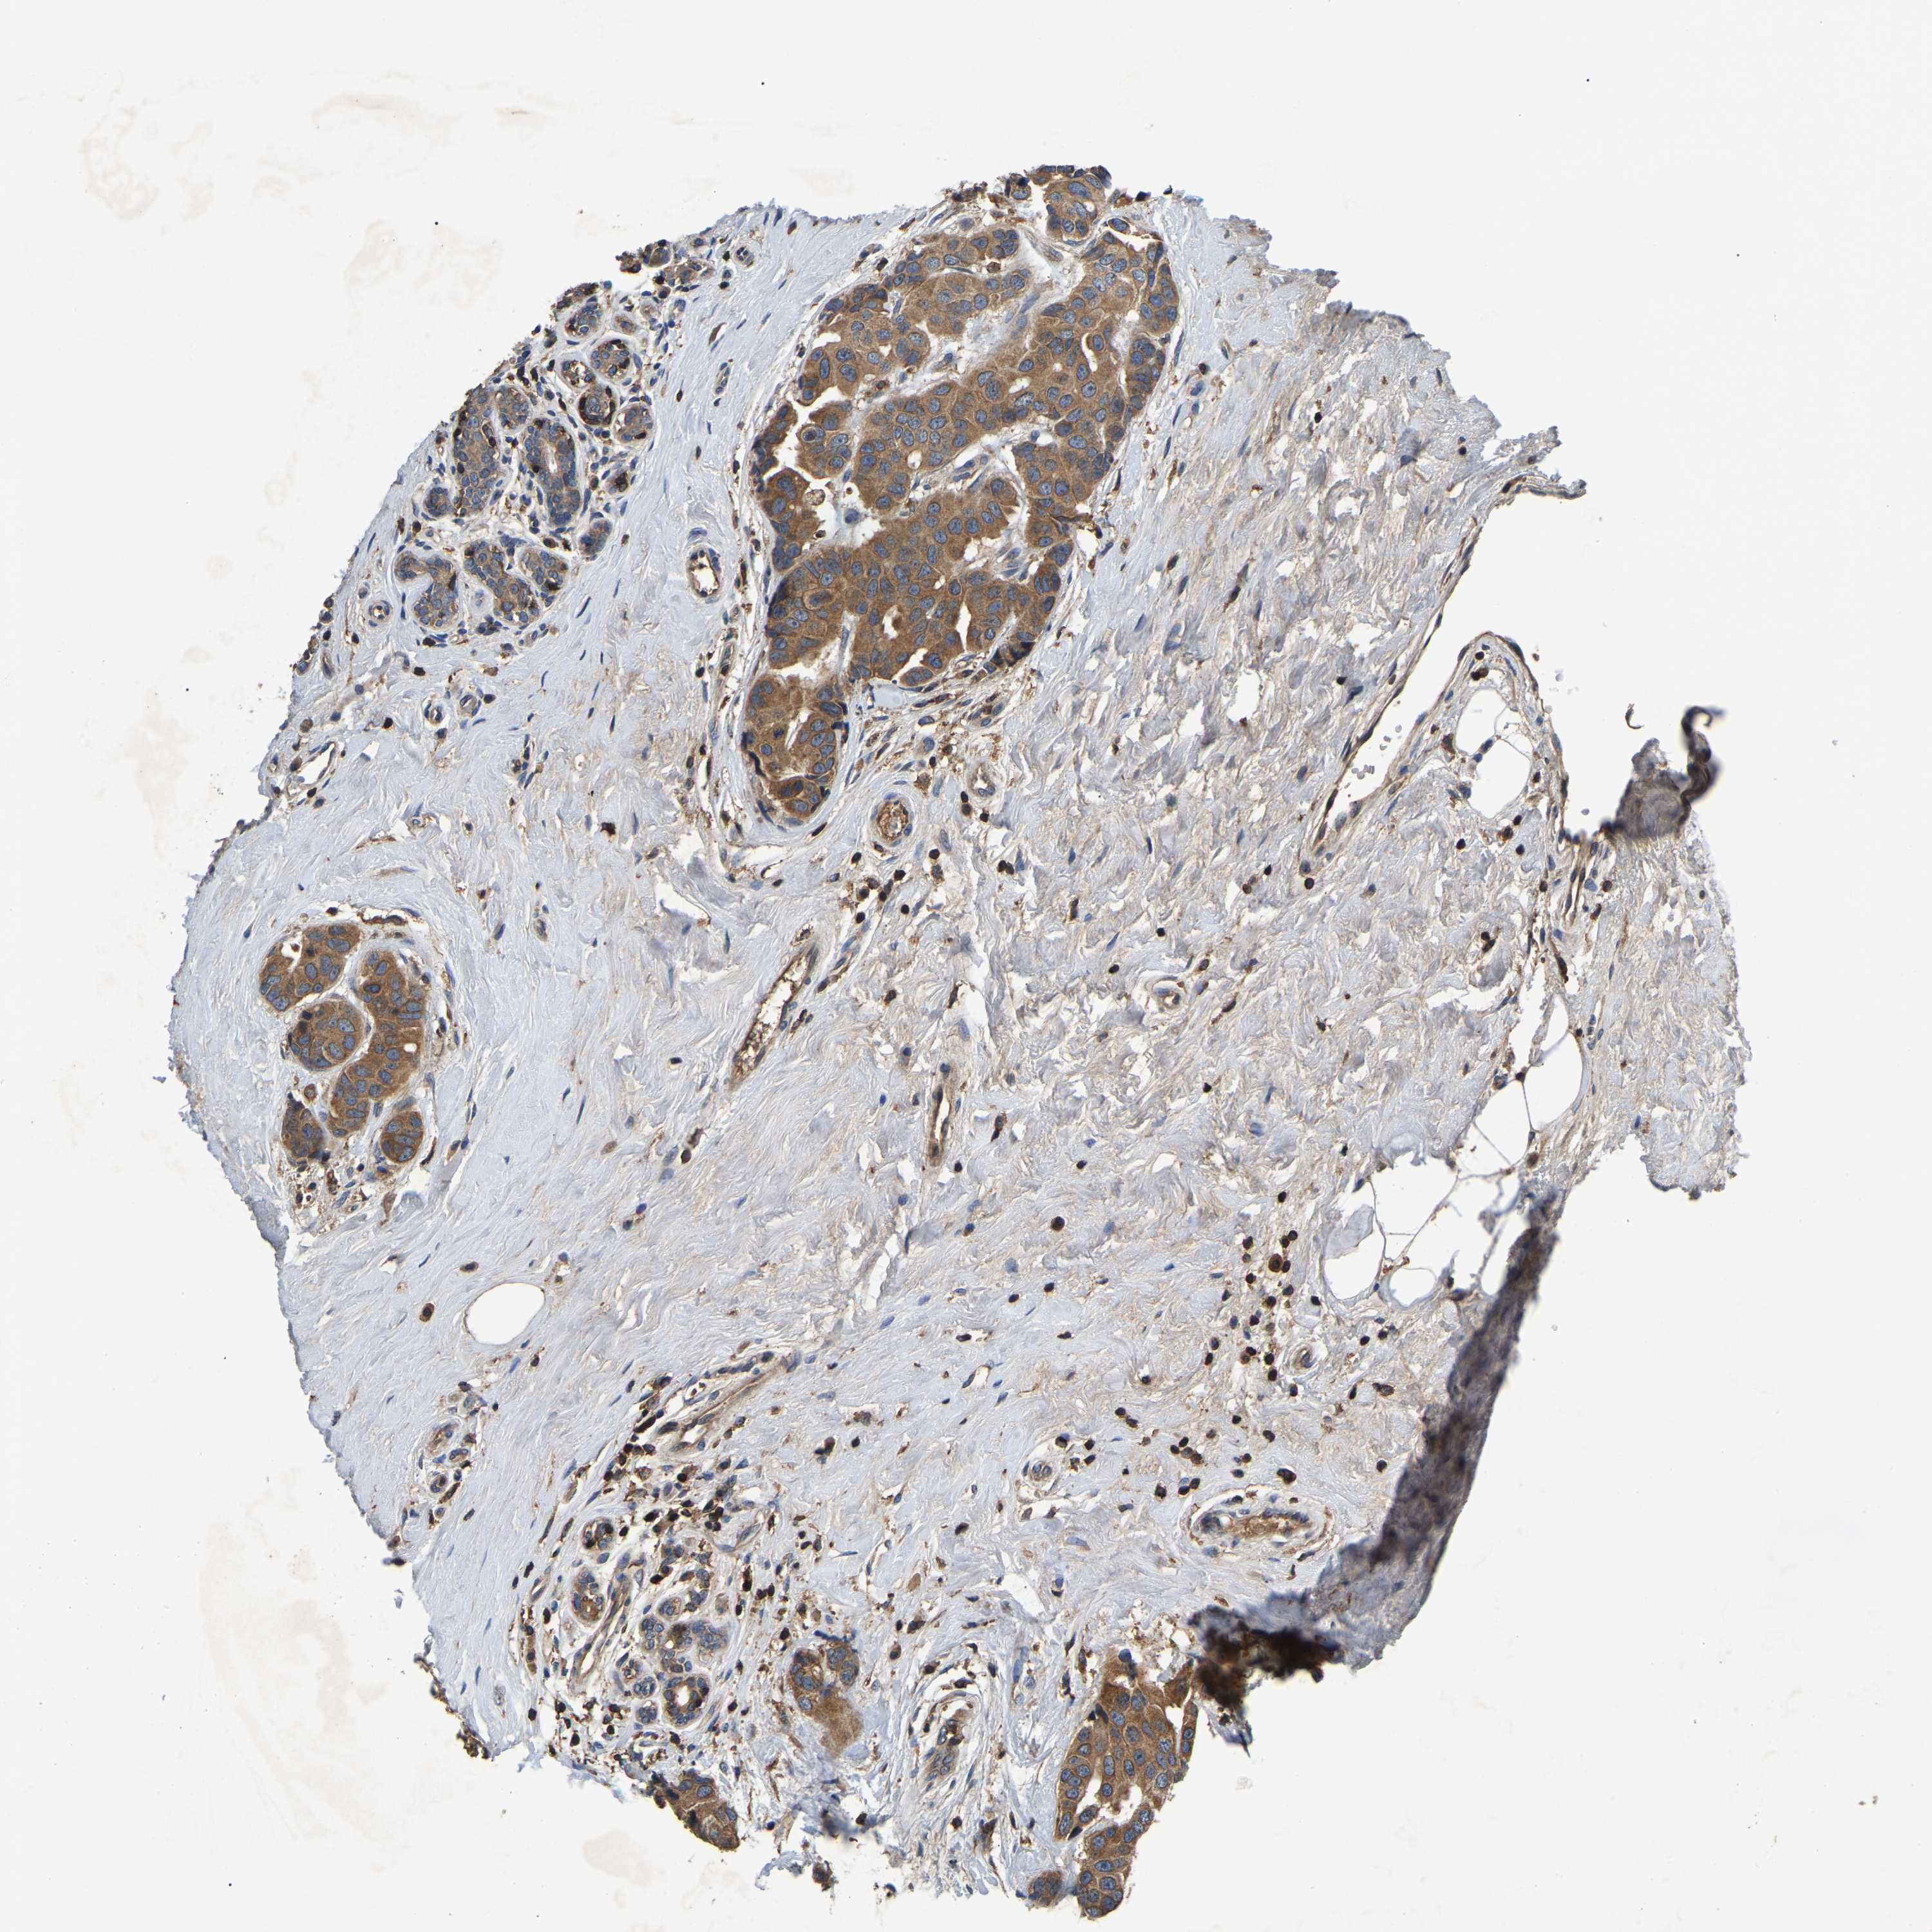

CANCER BREAST CANCER Show tissue menu

BRCA TCGA BRCA VALIDATION PROTEIN EXPRESSION

Breast cancer

Human cancer

SMPD2 is not prognostic in Breast Invasive Carcinoma (TCGA)